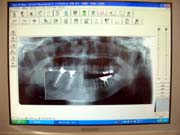

<デジタルレントゲン>

当院のレントゲン機器は、従来型に比べ、被曝量がおよそ1/10と少なく、患者様のお身体に非常に優しいものです。

又、廃液も出ませんので、地球にも優しいものとなっております。

さらに画像も鮮明であり、患部を拡大して見ることも出来ます。